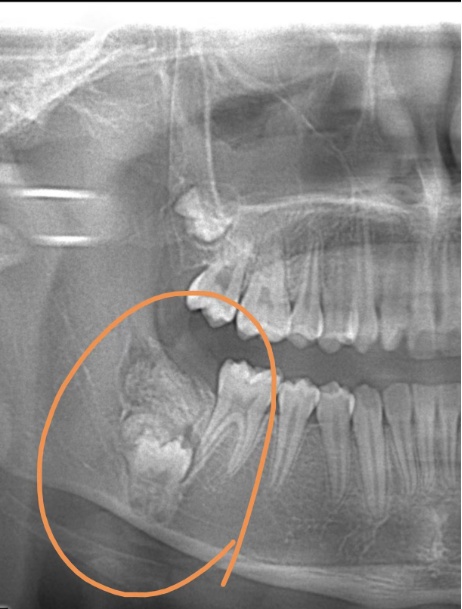

近日,12岁的小雅因为牙齿不齐前来上海市儿童医院口腔科做正畸治疗,拍片发现小雅的右下颌骨内发生了瘤样病变,因此导致其右下第二恒磨牙在顶出来的途中遇到“埋伏”,无法正常长出。

牙瘤是牙源性肿瘤中的一种,生长于颌骨内,是以牙体组织杂乱排列成团或形成数量不等的畸形牙为特征的牙的发育畸形,并非真性肿瘤,瘤体内可含有不同发育阶段的各种牙胚组织或牙,数个至数十个不等,形状不规则,有的近似正常牙,有的只是一团紊乱的硬组织,周围包裹着一层纤维膜。

牙瘤病因较复杂,多种因素均可能与牙瘤的发生相关,如乳牙的慢性炎症和感染遗传因素、成牙本质细胞过度反应等,均可能导致牙瘤发生,牙瘤患者常有缺牙现象,牙瘤可引起恒牙迟萌、疼痛、颌骨膨隆、邻牙移位、松动,病变范围较大,可导致骨缺损甚至引起骨折。

牙瘤手术的实施难度与瘤体生长的位置有关,如果牙瘤处于颌骨内,需要在右下颌后牙区开展手术,术野范围局限以及埋伏恒牙临近下牙槽神经区域,会增加手术难度和术中风险。

小雅的牙瘤就生长在颌骨内,手术难度较大,但在手术中,口腔科团队使用了最新的超声骨刀微创去骨法,尽量保留正常的颌骨组织,最大程度保护黏膜组织及正常的恒牙。而且,手术在全麻下进行,医生在足够空间视野下操作,减少了手术时长,最大限度地减轻了患儿心理上的恐惧和身体上的疼痛。